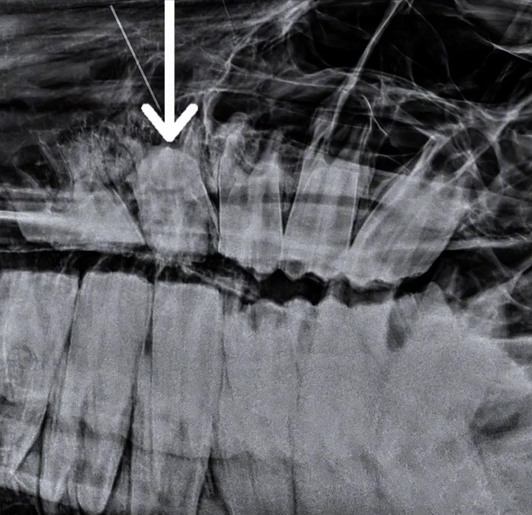

НА ВИДЕО: На осмотре у данного пони отмечалось появление свищевого хода в области верхней челюсти. Был выявлен патологический зуб с частичной фрагментацией коронки, изменение положения относительно зубного ряда в левую сторону. Это вызывало у пациента дискомфорт и болезненные ощущения. Было решено удалить этот «беспокоящий» зуб.

Рентгенологическое обследование также подтвердило наличие апикальной инфекции и скученность зубного ряда. Кроме того, по результатам рентгена и стоматологического осмотра на данном зубном ряду обнаружена гиподонтия, что также указывает на врожденую аномалию.